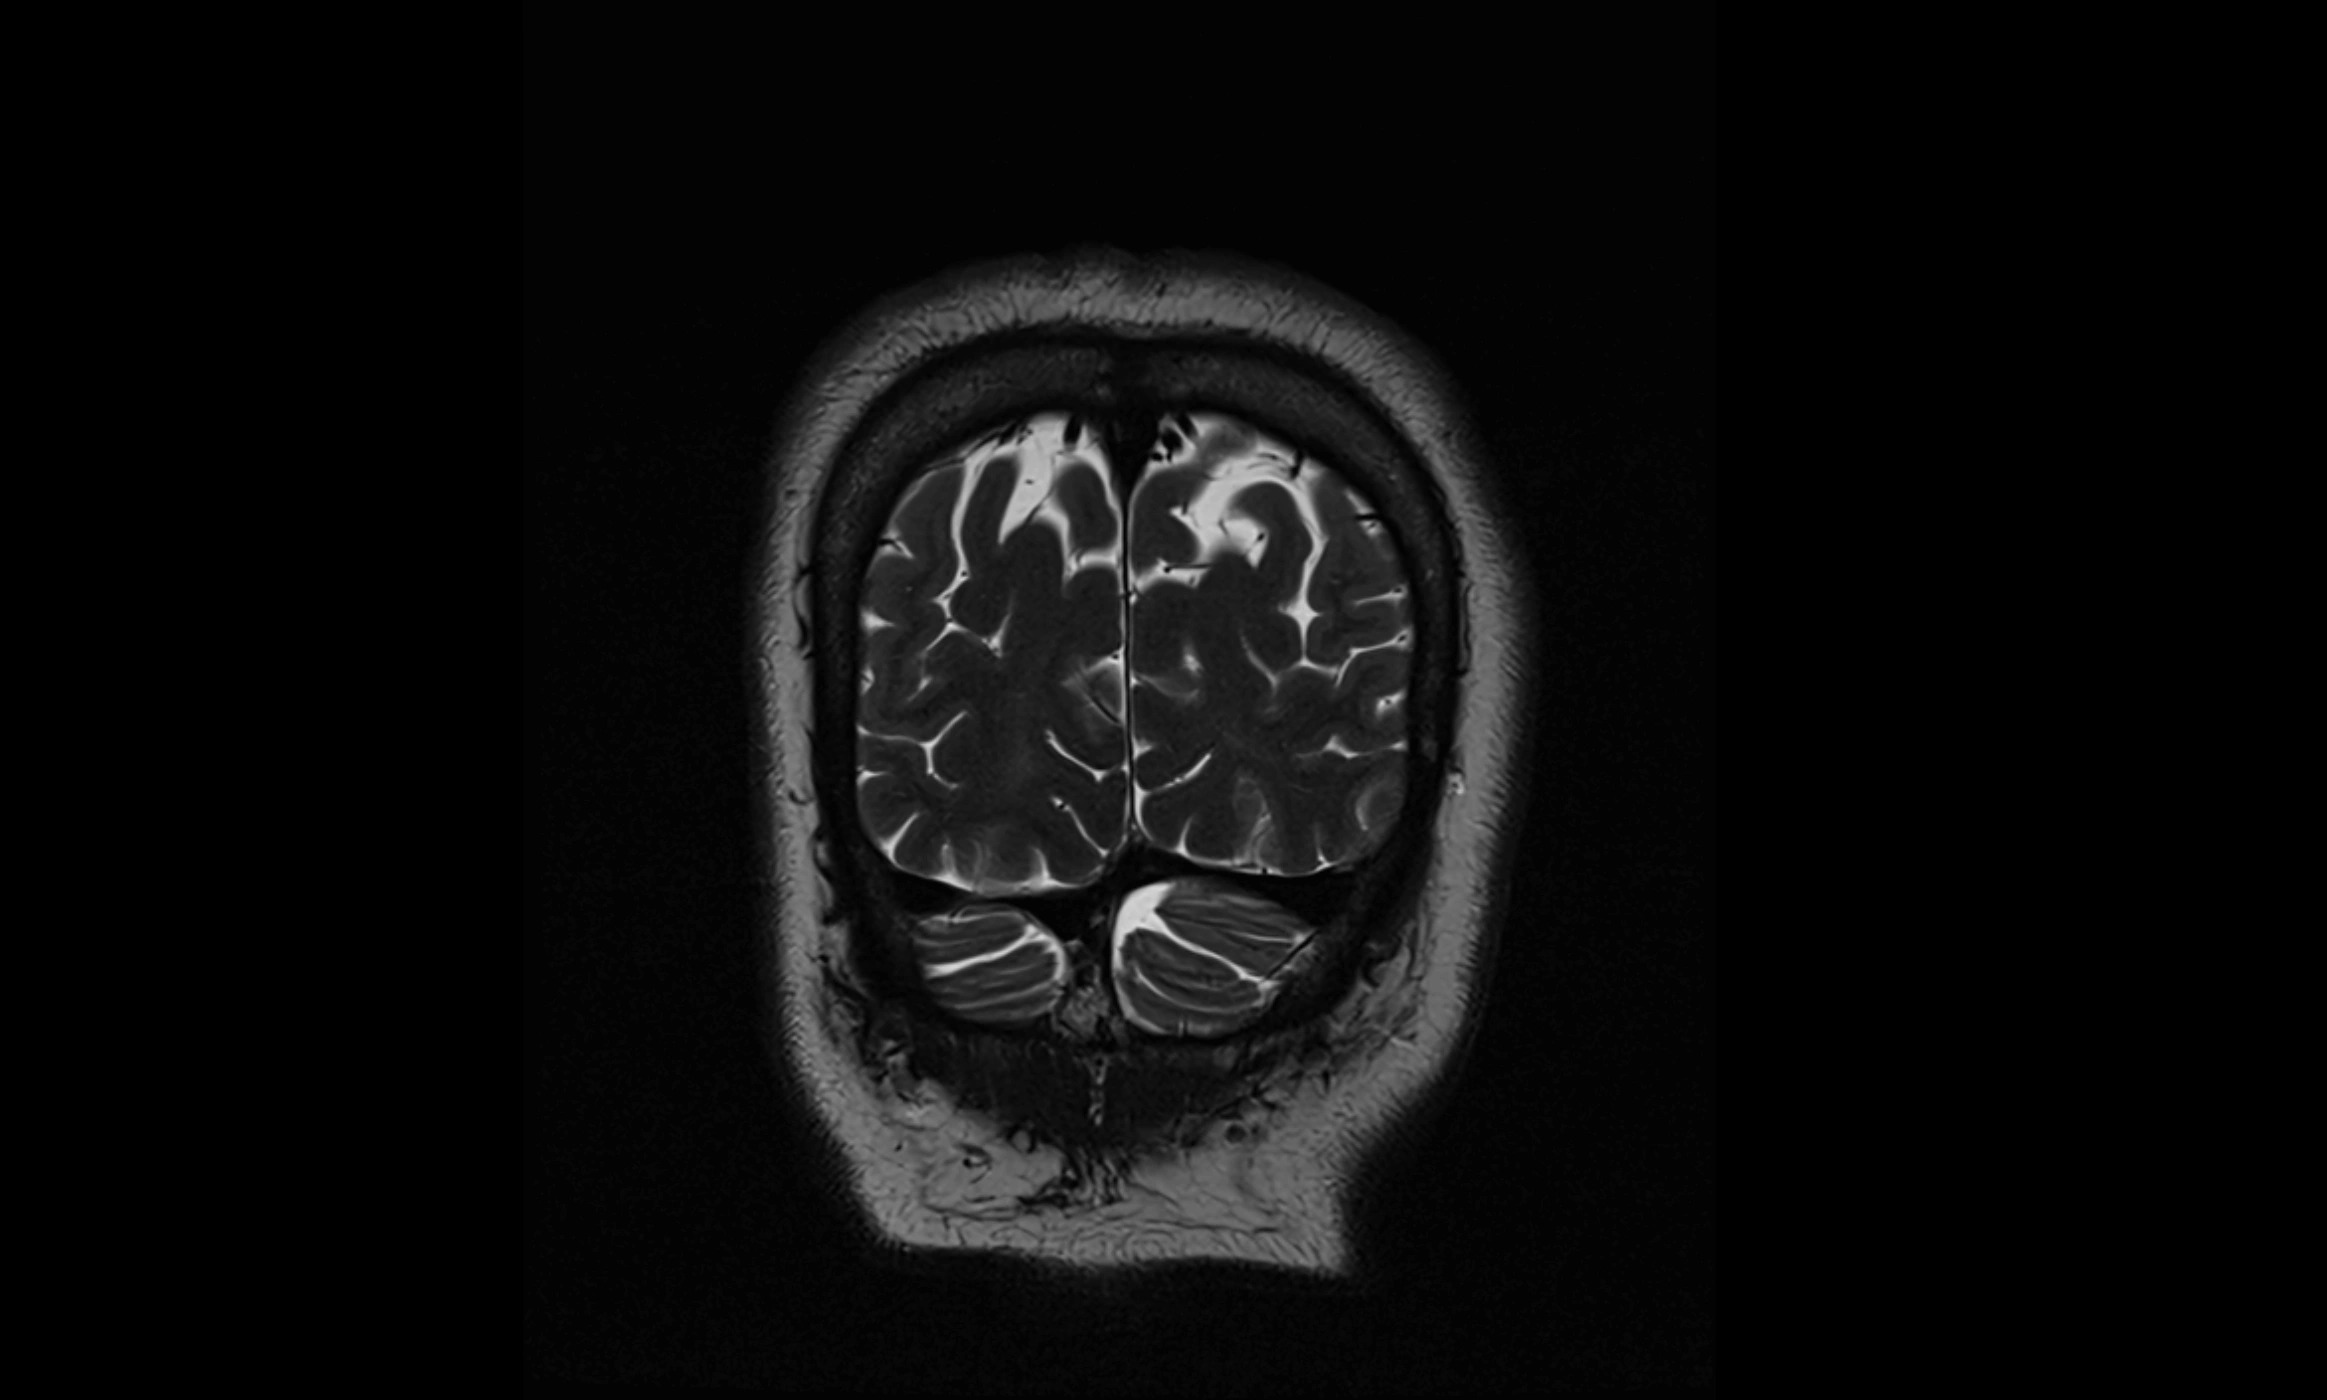

MRI images

image